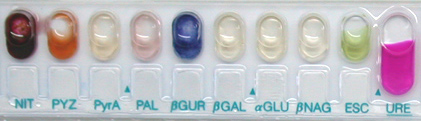

- Une galerie API® CORYNE est réalisée dont voici le résultat après 18 h d'incubation à 37°C en atmosphère ambiante :